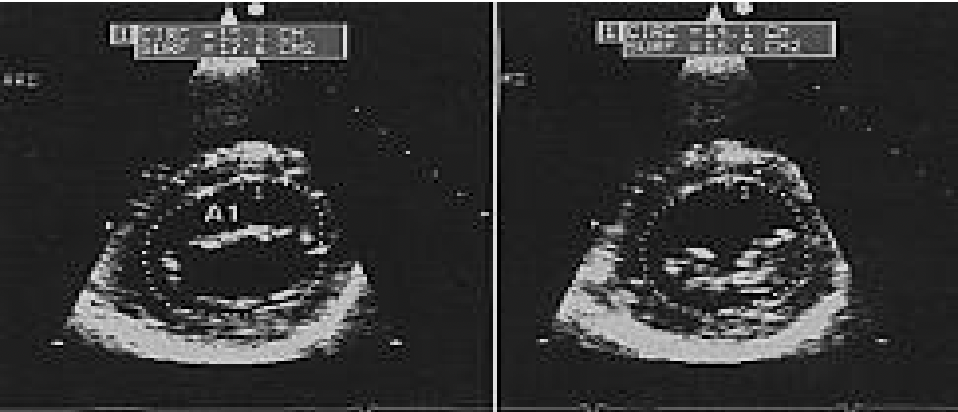

- Đo phân số tống máu thất trái bằng phương pháp Simpson.

Hình 9. Đo phân số tống máu thất trái bằng phương pháp Simpson